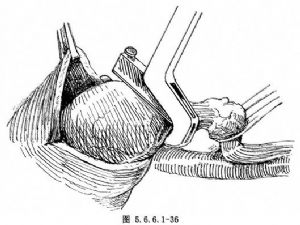

在靠近贲门口的Kocher钳下缘0.5cm处做一浆肌层荷包缝线,暂不打结,准备经此放置吻合器主体。如果肿瘤浸润至贲门部,则距病变边缘4~6cm用胃残端缝合器进行缝合、关闭,之后在两排缝合钉之间切断胃(图5.6.6.1-36,5.6.6.1-37)。